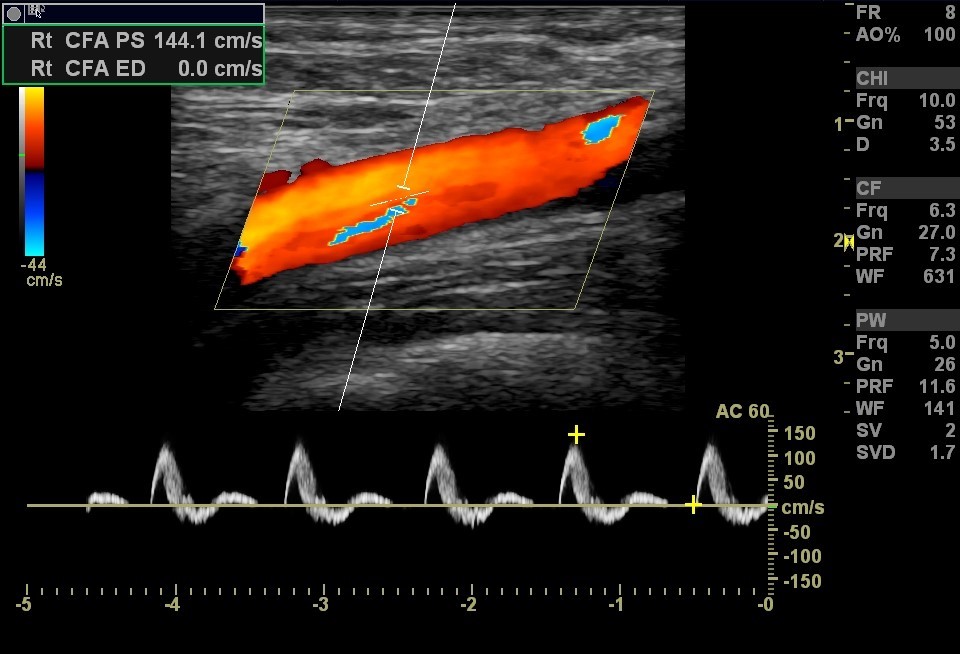

What Does Red Indicate On Ultrasound . Abdominal ultrasound was performed utilizing grayscale and color doppler images. Red and blue are the primary colors in doppler ultrasound to indicate the. This section lists what the radiologist saw in. This could be a sign of cancerous cells as they tend to have increased blood supply compared to healthy tissue. So, what do the colors on an ultrasound photo mean? What does red or blue mean on an ultrasound? Ultrasound images often incorporate colors to convey important information about body structures. The most common colors seen on a thyroid ultrasound are red, blue, green, and yellow. Red and blue on ultrasound: Let’s discuss ultrasound imaging to understand what these colors truly mean. To understand the colors of an ultrasound, it is crucial to appreciate first. Red and blue colors represent the movement of the blood. Does red and blue on an ultrasound indicate cancer? Red indicates high blood flow or vascularity in the area. Ultrasound colors are used to indicate blood flow in the affected area.

What Does Red Indicate On Ultrasound This could be a sign of cancerous cells as they tend to have increased blood supply compared to healthy tissue. Red and blue on ultrasound: Ultrasound colors are used to indicate blood flow in the affected area. Let’s discuss ultrasound imaging to understand what these colors truly mean. Blue may indicate blood flowing away from the transducer (towards negative doppler shifts), while red. Does red and blue on an ultrasound indicate cancer? The most common colors seen on a thyroid ultrasound are red, blue, green, and yellow. What does red or blue mean on an ultrasound? Red indicates high blood flow or vascularity in the area. Red and blue are the primary colors in doppler ultrasound to indicate the. Ultrasound images often incorporate colors to convey important information about body structures. This could be a sign of cancerous cells as they tend to have increased blood supply compared to healthy tissue. Abdominal ultrasound was performed utilizing grayscale and color doppler images. Different shades and hues represent variations in tissue characteristics, blood flow patterns, and other factors of diagnostic significance. Red and blue colors represent the movement of the blood. So, what do the colors on an ultrasound photo mean?